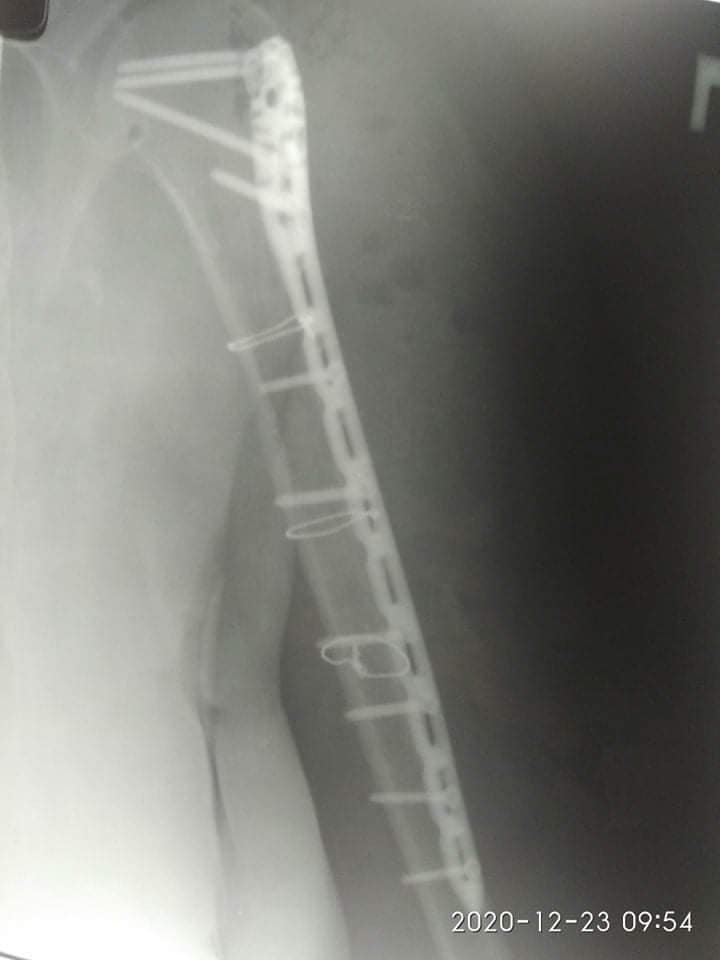

Діагноз: Закритий багатовідламковий перелом діафізу правої плечової кістки", - йдеться в дописі.

21 грудня їй провели 4-ьох годинну операцію - остеометалосинтез правої плечової кістки за допомогою LCP проксимальної Philos пластини та гвинтів.